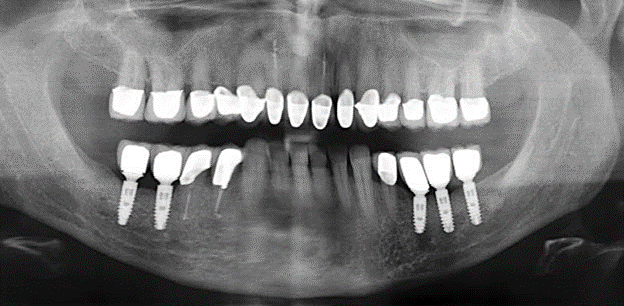

Fig. 1: Panoramic radiograph of initial situation in 2004.

Description of patient case

A 52-year-old patient presented in our clinic for the first time in 2004 following tooth loss in the third quadrant, expressing a desire for a new prosthetic restoration. Periodontal and radiological diagnostics revealed the need for extensive periodontological treatment. In addition, teeth 48, 28 and 27 were attributed a very poor prognosis and were subsequently extracted (Fig. 1). Following the successfully completed, systematic periodontological treatment, a fixed dental implant was inserted with the introduction of five implants in tooth regions 35, 36, 37, 46 and 47. Prosthetic treatment of the natural teeth was effected with veneered zirconium dioxide ceramic crowns; the implants were composed of two-piece, individual zirconium dioxide abutments and similarly veneered crowns made of a zirconium dioxide ceramic (Cercon base colored, Dentsply Sirona Lab). Definitive insertion of the prosthetic restoration occurred in 2005.